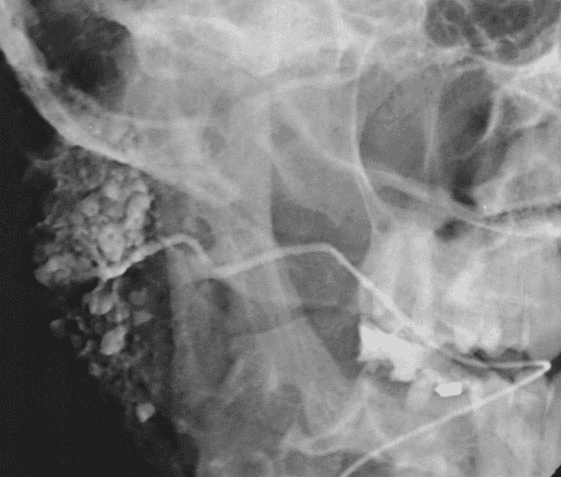

Sialolithiasis

Obstruction or strictures

Infection

Recurrent pain and swelling

Dry mouth

Traumatic injuries

Lesions, tumors

When normal radiography is inconclusive